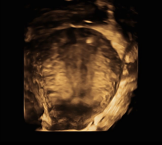

A plain abdominal radiograph demonstrated an IUCD positioned abnormally within the pelvis (Figure 1). Two-dimensional transvaginal ultrasonography re vealed a hyperechogenic focus near the uterine fun dus, raising suspicion of uterine perforation (Figure 2). Three-dimensional transvaginal imaging offered superior anatomical detail, clearly demonstrating: an empty uterine cavity, partial extrusion of the IUCD through the posterior lower uterine segment into the peritoneal cavity, and a hyperechogenic spot corres ponding to fundal trauma, likely resulting from a prior unsuccessful blind retrieval attempt (Figures 3–8). These findings confirmed uterine perforation with partial migration of the device.

Figure 3. This shows the area of perforation at the fundus on 3D

Figure 4. Shows the site of fundal perforation with uterine sound